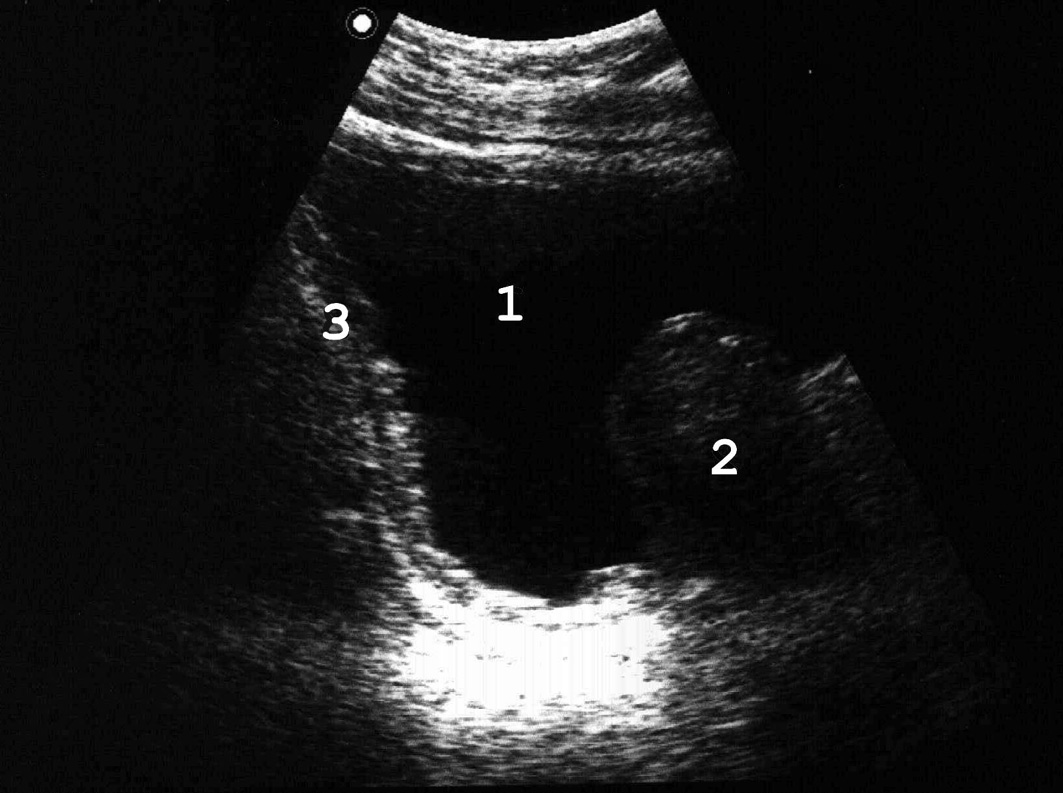

Мочевой пузырь представляет собой полый орган, расположенный в малом тазу, за лонным сочленением. Емкость пузыря от 200 до 600 мл, в патологических условиях может достигать 1000−2000 мл. У здорового человека первый позыв на мочеиспускание возникает при объеме мочевого пузыря 100−150 мл, выраженный позыв − при заполнении 250−350 мл. Анатомически в мочевом пузыре различают верхушку, шейку, дно и тело. Верхушка − место перехода пузыря в среднюю пузырно-пупочную связку, различима только при его наполнении (1 − см. рис. 1). Дно (4) − наиболее широкая нижнезадняя часть мочевого пузыря, обращенная у мужчин в сторону прямой кишки, у женщин в сторону матки и верхней части передней стенки влагалища. Шейка − суженная часть мочевого пузыря, граничит с мочеиспускательным каналом. Средний отдел, расположенный между верхушкой и дном мочевого пузыря, называется телом. мочевой пузырь имеет переднюю, заднюю и две боковые стенки (2, 3), переходящие одна в другую без четких границ. Мочепузырный треугольник Льето (5) образован устьями мочеточников и внутренним отверстием мочеиспускательного канала, основанием его является межмочеточниковая складка. Начальный отдел мочеиспускательного канала охватывается предстательной железой (6).

Рис. 1. Сонограмма мочевого пузыря мужчины в норме. Остаточный объем мочи с достаточной для практики точ¬но-стью можно определить по формуле a х b x c x 0,57 [50]. (Поперечное [A] и продольное [Б] сканирование, конвексный датчик 5 МГц, “Logiq-500”).